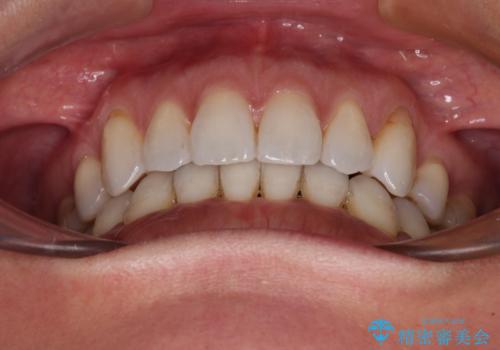

抜歯矯正の後戻りをインビザライン・ライトで解消

- 下顎前歯を中心に、以前行った矯正治療の後戻りが気になるとのことで来院された患者様です。

後戻りは軽度であったため、インビザライン・ライトにて治療を行うこととしました。

矯正治療後は、再度後戻りすることを極力回避するために、下顎前歯の舌側を細いワイヤーを用いて保定することとしました。